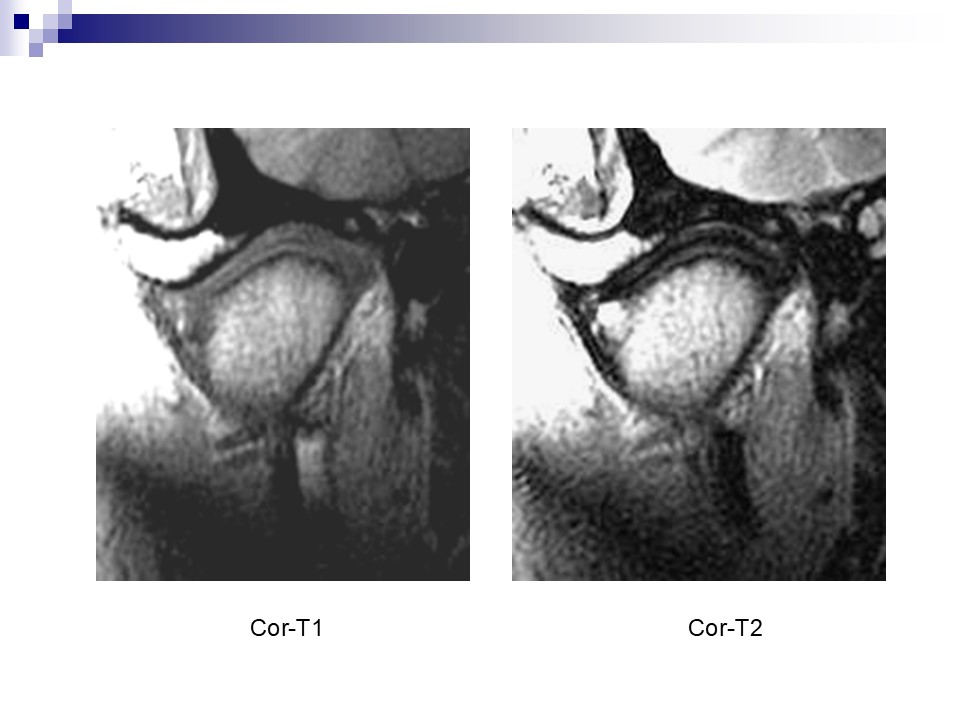

“颞下颌关节的磁共振成像PPT” 的相关文章